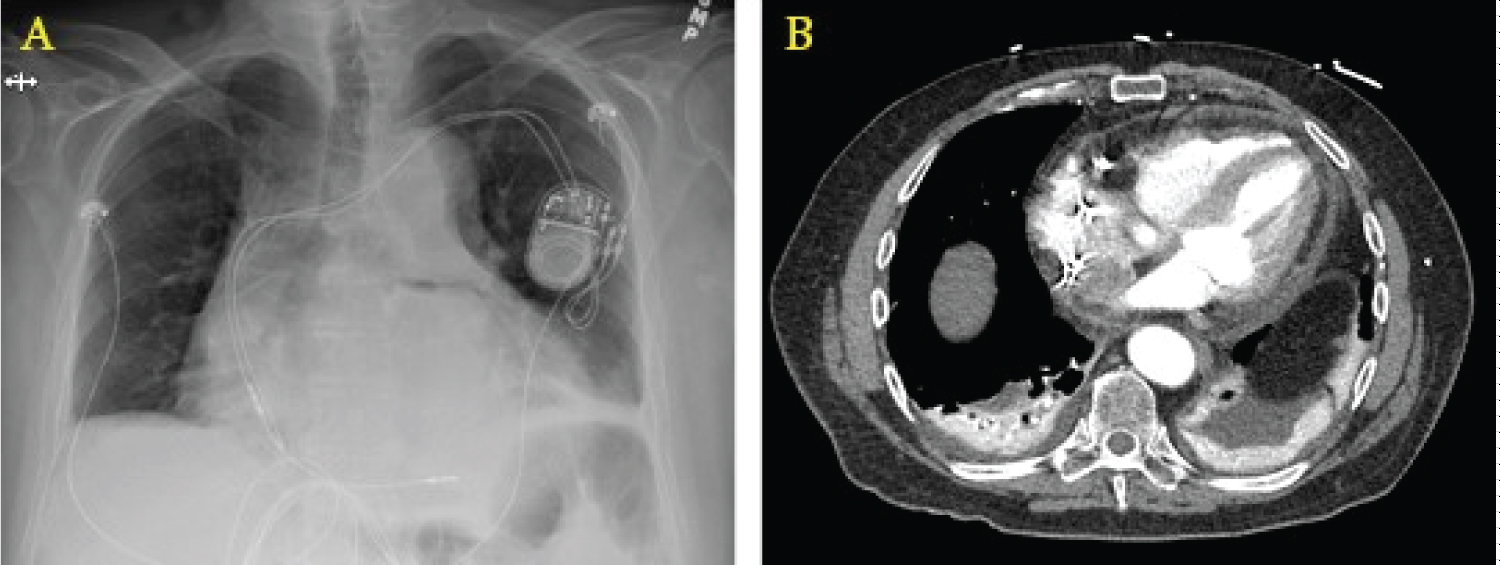

A chest X-ray may show a widened mediastinum or pneumomediastinum; if oral contrast is used as in a fluoroscopic swallow study, a leak may be seen during the imaging series. Computed tomography scanning with intravenous and oral contrast is the best imaging study at this point and is usually only positive late in the course of the disease, with findings including pneumomediastinum or pneumopericardium (Figure 2) [34]. The morbidity and mortality of open surgical operations for repair are high, but compared to conservative medical therapy or endoscopic stenting, early surgical intervention provides the best chances of survival [35], as earlier studies have shown almost 100% mortality by endoscopic stenting of the perforation [36]. Options for surgical repair include: 1) Median sternotomy with full use of cardiopulmonary bypass, patch repair of atrial defect from within the left atrium, followed by endoscopic stenting of the esophagus; 2) Right thoracotomy with femoral-femoral bypass, patch repair of atrial defect from either within or external to the left atrium, followed by placement of a pedicled muscle flap between the esophagus and atrium [37]; and 3) Median sternotomy with full use of cardiopulmonary bypass, patch repair of the atrial defect from within the left atrium, followed by left thoracotomy for positioning of the muscle flap between the esophagus and left atrium.

Figure 2: Radiographic findings of AEF. (a) Widened mediastinum on chest X-ray; (b) Computed tomography showing pneumopericardium with air tracking up the ascending aorta.